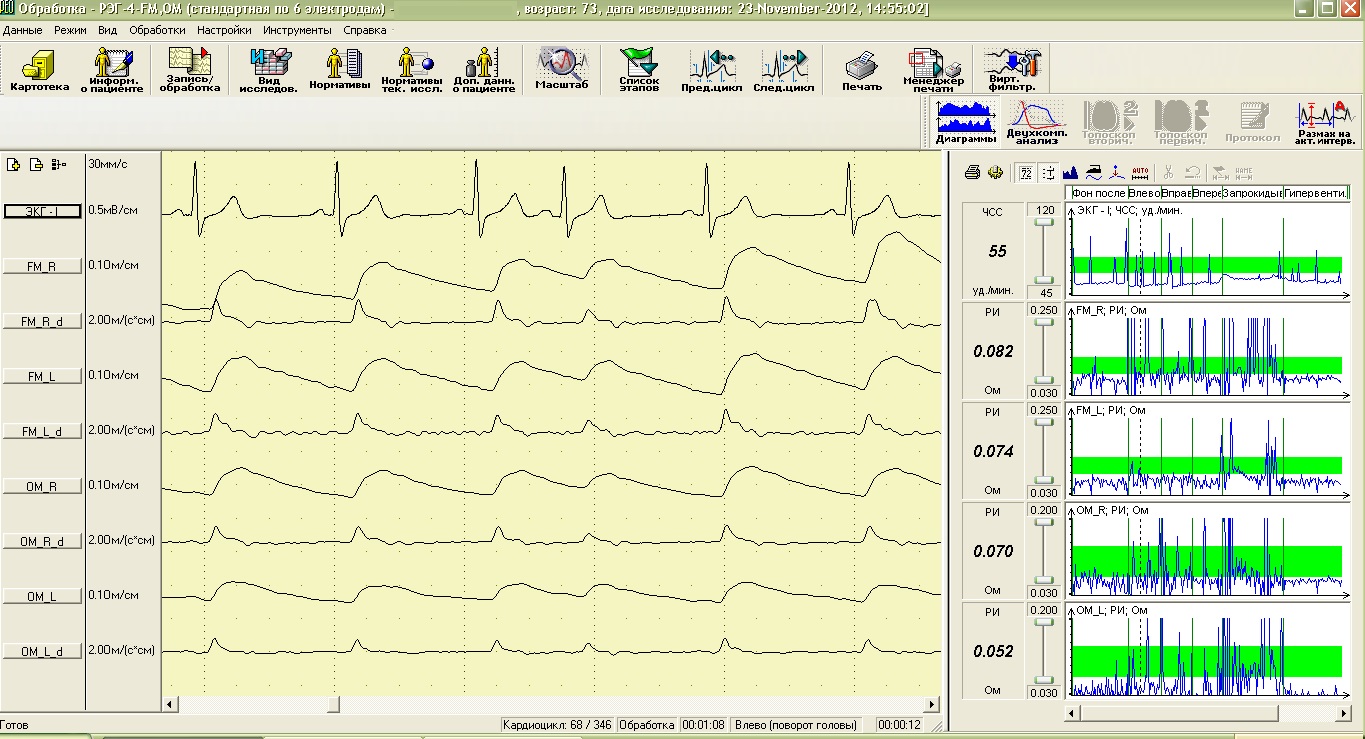

Параллельно с инструментальной регистрацией функций мозга желательно проверить состояние сосудов головного мозга, в которых, как правило, с возрастом регистрируются изменения лимфовенозного или микроциркуляторного отделов кровообращения, а порой, и состояния магистральных артерий. Особенно важно проверить функциональные особенности работы сердца (даже при отсутствии жалоб) и определить тип кровообращения, что в дальнейшем позволит врачам разрабатывать методики для поддержания оптимального функционального состояния и сосудов, и работы сердца.

Реоэнцефалографическое исследование сосудов головного мозга в состоянии покоя

Реоэнцефалограммы основных сосудов, питающих мозг